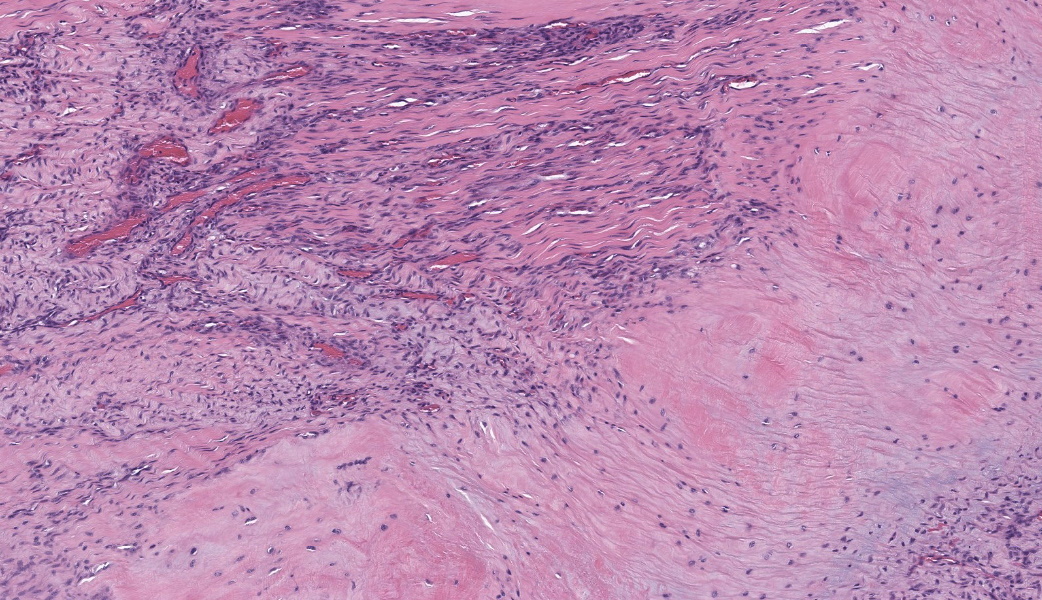

Suspensory ligament, right rear branch. Compared to a branch of the clinically normal right front suspensory ligament, collagen fibers are irregular and often form intersecting or divergent bundles. In many areas, there are fewer fibroblasts among collagen fibers than in the normal control. Throughout the tissue, wavy tendrils of pale basophilic, Alcian blue-positive matrix dissect between collagen bundles. Similar material surrounds increased numbers of variably sized, dilated and tortuous blood vessels. These vessels have thin walls and are lined by plump endothelial cells, and are often surrounded by loosely arranged stellate cells. In other areas, there is chondroid metaplasia, with clustered and individual chondrocyte-like cells in lacunae surrounded by amorphous, pale basophilic matrix, which is sometimes faintly mineralized. There is rare hemorrhage.Contributor's Morphologic Diagnoses:

The terms degenerative suspensory ligament desmitis (DSLD) and suspensory ligament degeneration (SLD) are used somewhat synonymously, with DSLD often used to describe horses with a clinical diagnosis of suspensory ligament degeneration, and SLD used to describe histologic findings in the suspensory ligaments of horses that may or may not have a clinical diagnosis of DSLD. DSLD causes chronic, progressive multi-limb lameness of variable severity, often recognized by enlarged, hyperextended or dropped fetlocks.8 The rear limbs are typically more affected.3,8 In addition, the terms suspensory ligament desmitis or suspensory ligament desmopathy may be used to describe any of a variety of clinically or ultrasonographically detected injuries anywhere along the length of the suspensory ligament.3 Histology is rarely performed in these cases, especially in the acute phase, and it is unclear if these injuries are related to degenerative changes.3Histologic changes in SLD/DSLD include loss of longitudinal arrangement of collagen fibers, proteoglycan accumulation, presence of chondrocytes, hemorrhage, vascular proliferation, and widened interstitial connective tissue septa.4,6 Despite the use of the term desmitis, inflammatory cells are not present.4 These changes are reported to be more severe in the branches of the suspensory ligament than in the body or origin of the ligament.3,5

The major histologic findings within ligaments suffering from SLD include loss of longitudinal arrangement of collagen fibers (disorganization), proteoglycan accumulation (increased ground substance), presence of chondrocytes (chondroid metaplasia), hemorrhage, vascular proliferation, widened interstitial connective tissue septae, and a lack of inflammatory cells.8 As this disease develops, regardless of cause, degenerating collagen fascicles blend together and there is either death of the tenocytes/ligamentocytes or metaplasia of tenocytes/ligamentocytes into chondrocytes. Fibrosis develops within and around the ligament and is usually associated with hypertrophied tenocytes/ligamentocytes. These areas are generally interpreted as failed attempts at repair.